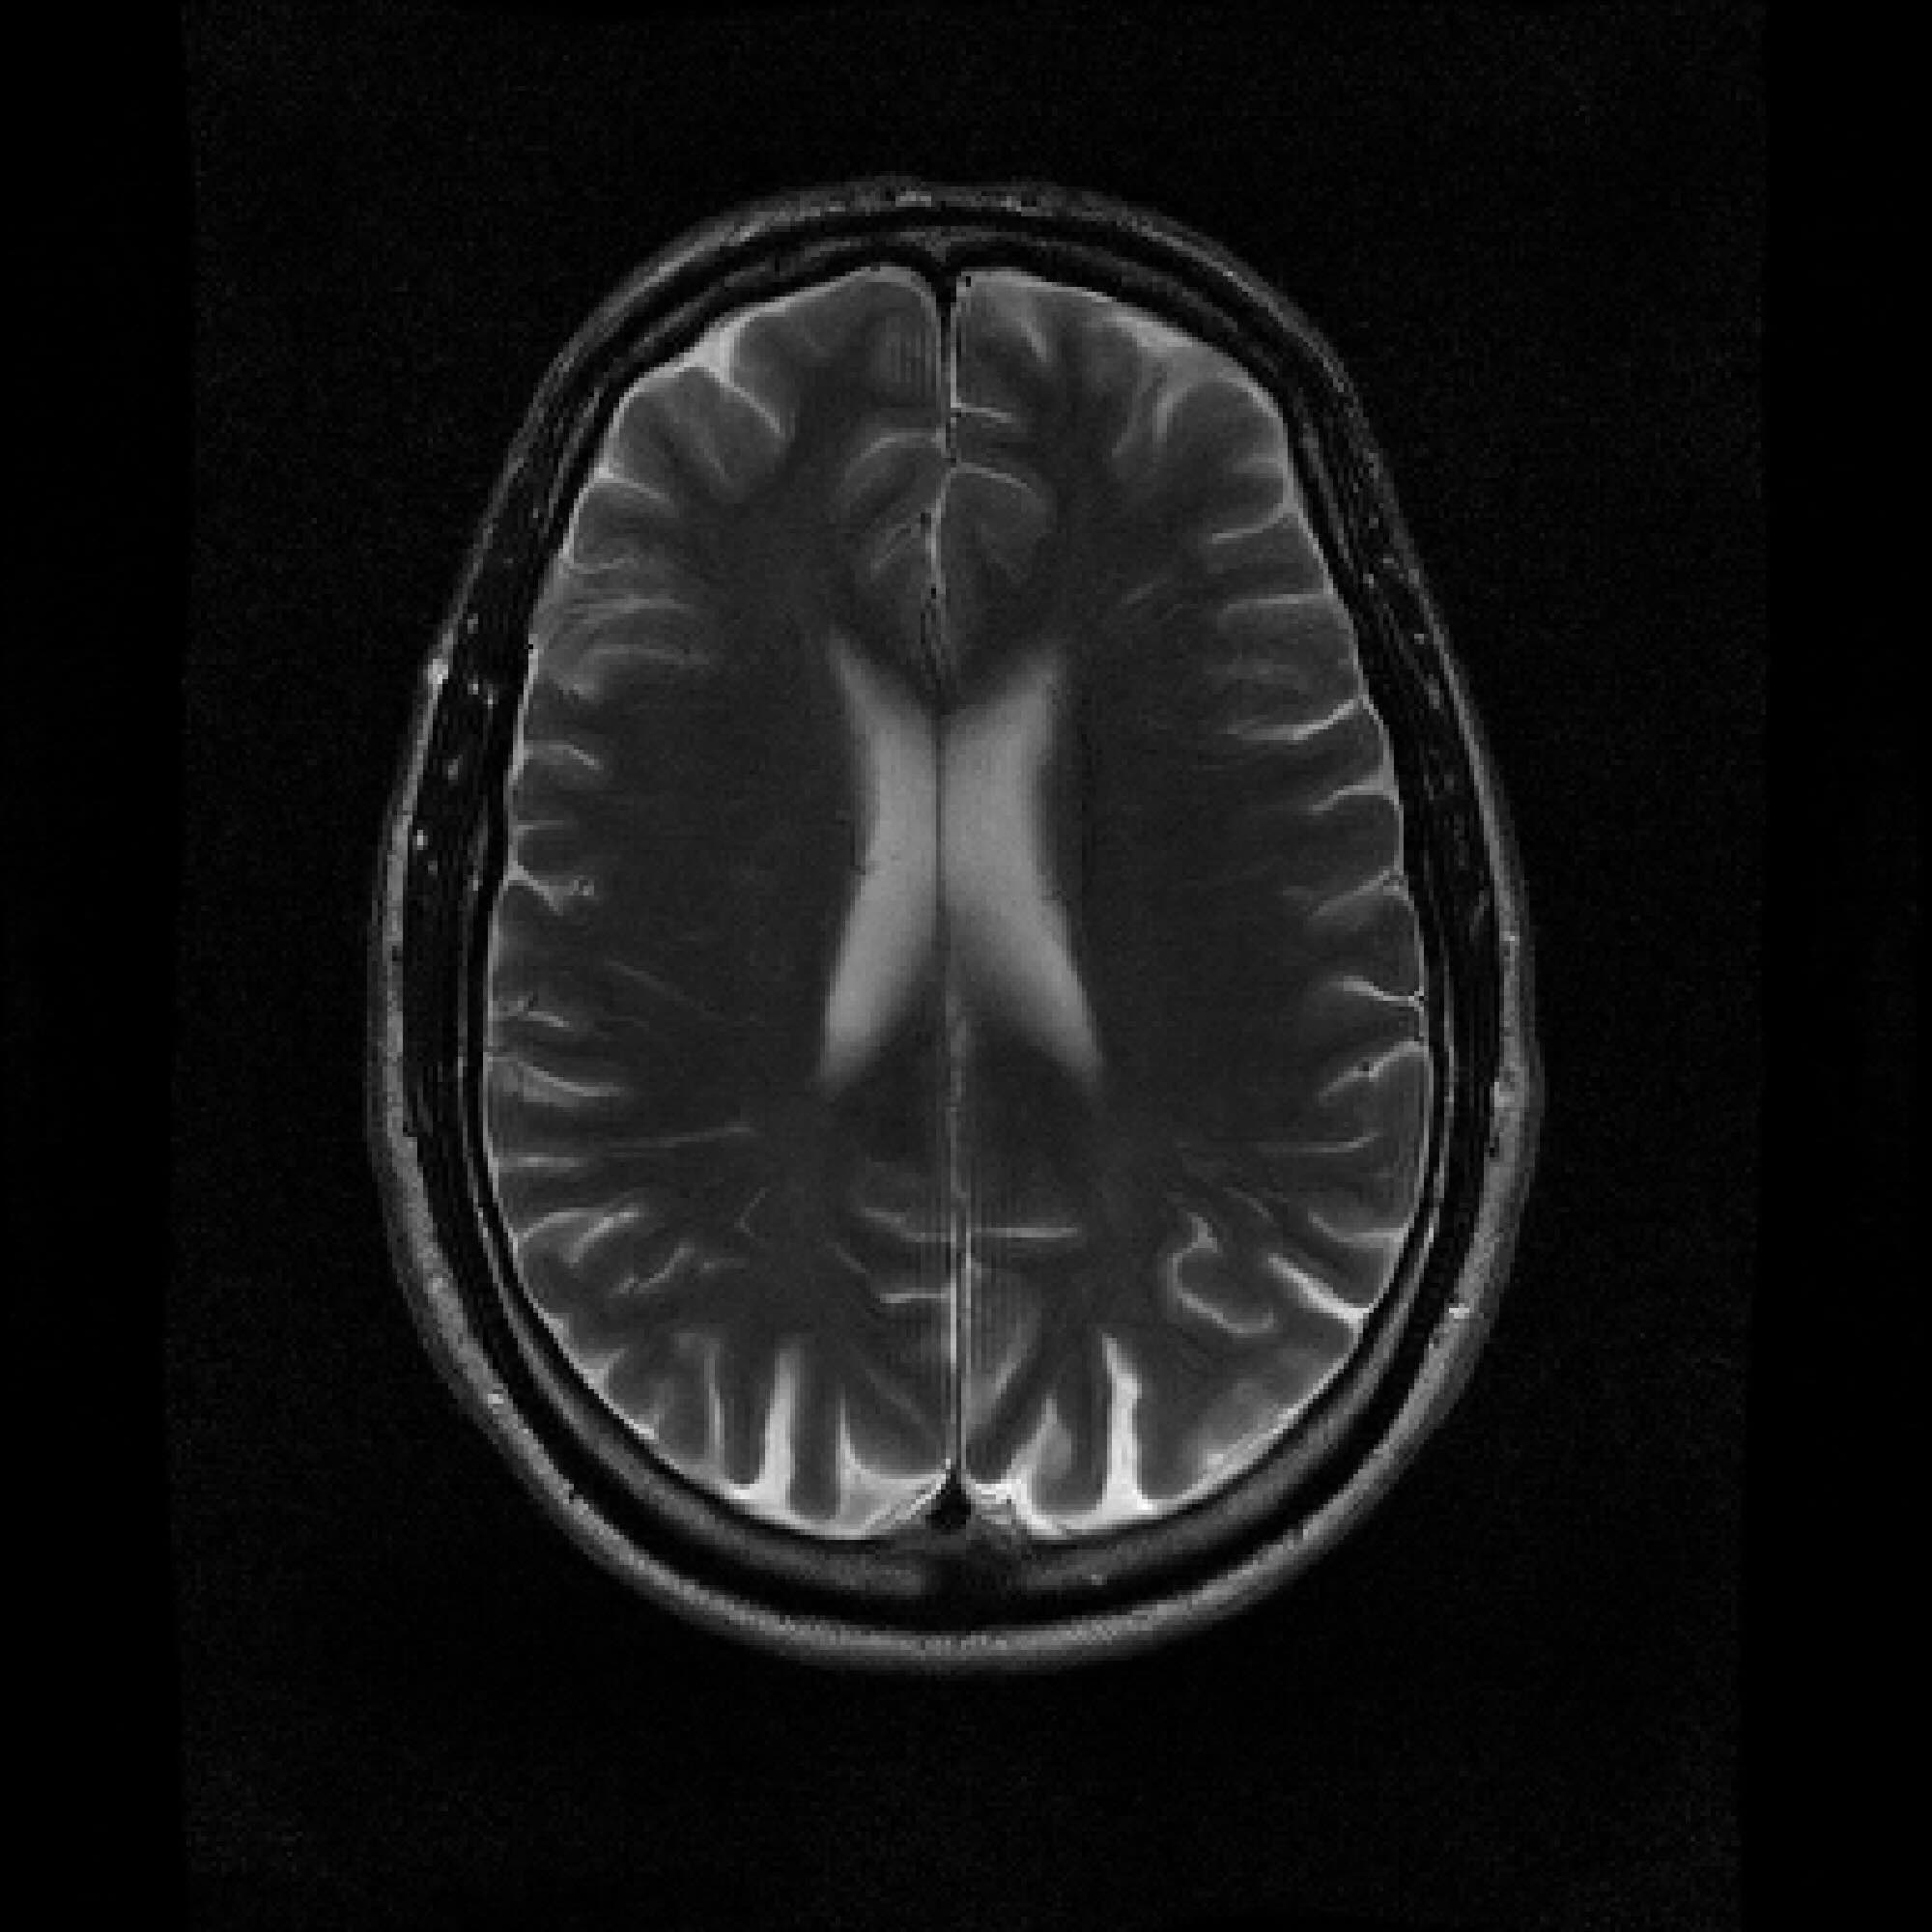

Refer to caption

Figure 2: Example MRI magnitude reconstructions with S=25S=25 training slices at acceleration (undersampling) factor R=7R=7. PaDIS-MRI reconstructions are sharper and more faithful to the fully-sampled ground truth. Insets are shown to the right to highlight detail.

Figure 2 provides a visual comparison of the reconstruction quality of each method on example slices. In reconstructions from the S=25,R=7S=25,R=7 models, FastMRI-EDM exhibits slightly more blurring and loss of fine structural details, particularly in regions with complex anatomical features. PaDIS-MRI, in contrast, preserves sharper boundaries and finer details. This enhanced data efficiency can be attributed to the patch-based prior’s ability to learn localized structural motifs more effectively from limited examples. Figure 6 in the Appendix shows similar reconstructions at S=200,R=7S=200,R=7 where FastMRI-EDM more closely approaches the performance of PaDIS-MRI but still struggles with highly detailed anatomy.